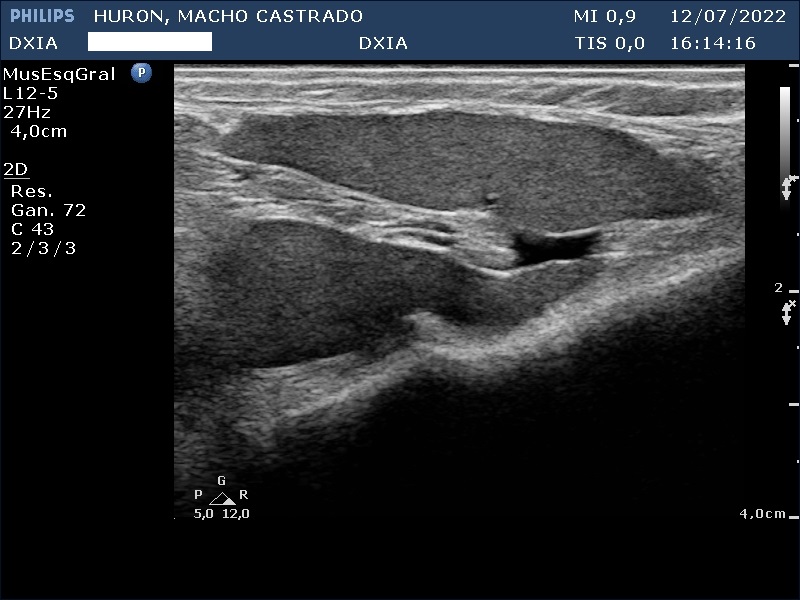

En esta ocasión os queremos presentar el caso de hurón (macho castrado) al que, debido a los síntomas que presentaba, tuvimos que realizarle un estudio ecográfico abdominal.

Presenta convulsiones así como hipoglucemias con picos de hiperglucemia por lo que su veterinario decide realizar un estudio de ecografía abdominal.